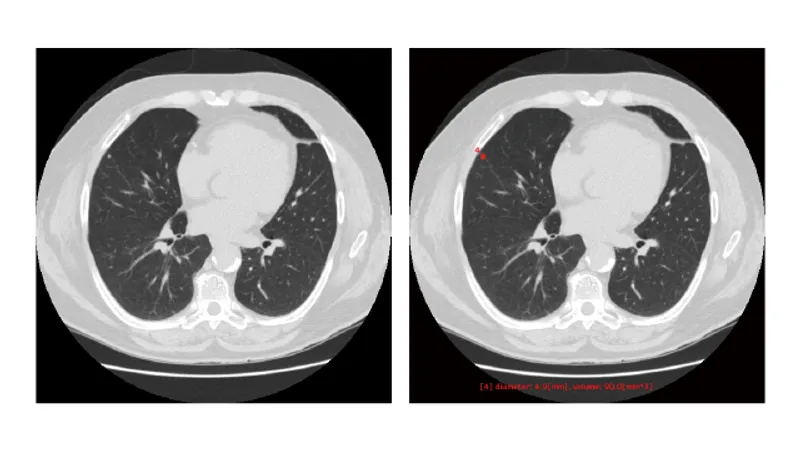

胸部CT画像から「関心領域」を抽出

本サービスは胸部 CT 画像における肺野領域の組織について、関心領域を抽出し体積と最大径を測定します。 また、関心領域の最大径が閾値以上であれば色付けを行います。

本サービスは、医師が設定した基準値に基づいてCT値を元に関心領域を抽出し体積と最大径を自動計測します。 また、関心領域の最大径が医師が設定した閾値以上であれば色付けを行います。